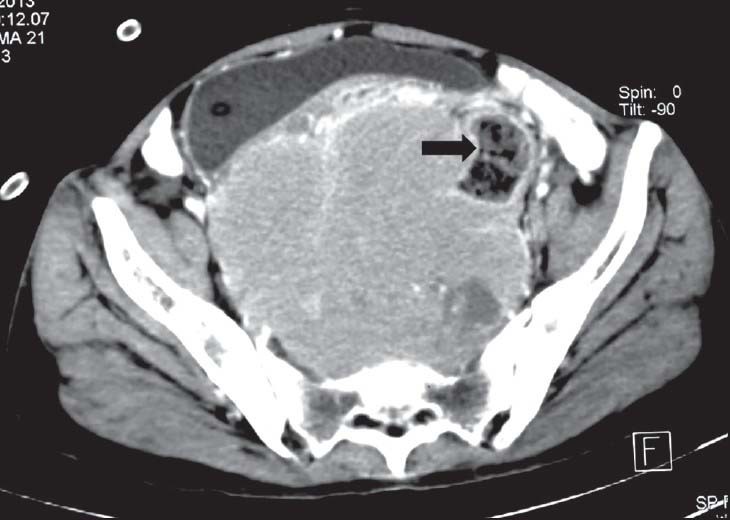

| Figure 5:Rectal gastrointestinal stromal tumors in a 49-year-old male — (a) barium enema spot image lateral view showing extrinsic impression on rectal wall (arrowhead) (b) axial contrast-enhanced computed tomography image showing heterogenously enhancing necrotic mass in pelvis (black arrowhead) displacing the urinary bladder (arrow) anteriorly

| Figure 5:Rectal gastrointestinal stromal tumors in a 49-year-old male — (a) barium enema spot image lateral view showing extrinsic impression on rectal wall (arrowhead) (b) axial contrast-enhanced computed tomography image showing heterogenously enhancing necrotic mass in pelvis (black arrowhead) displacing the urinary bladder (arrow) anteriorly